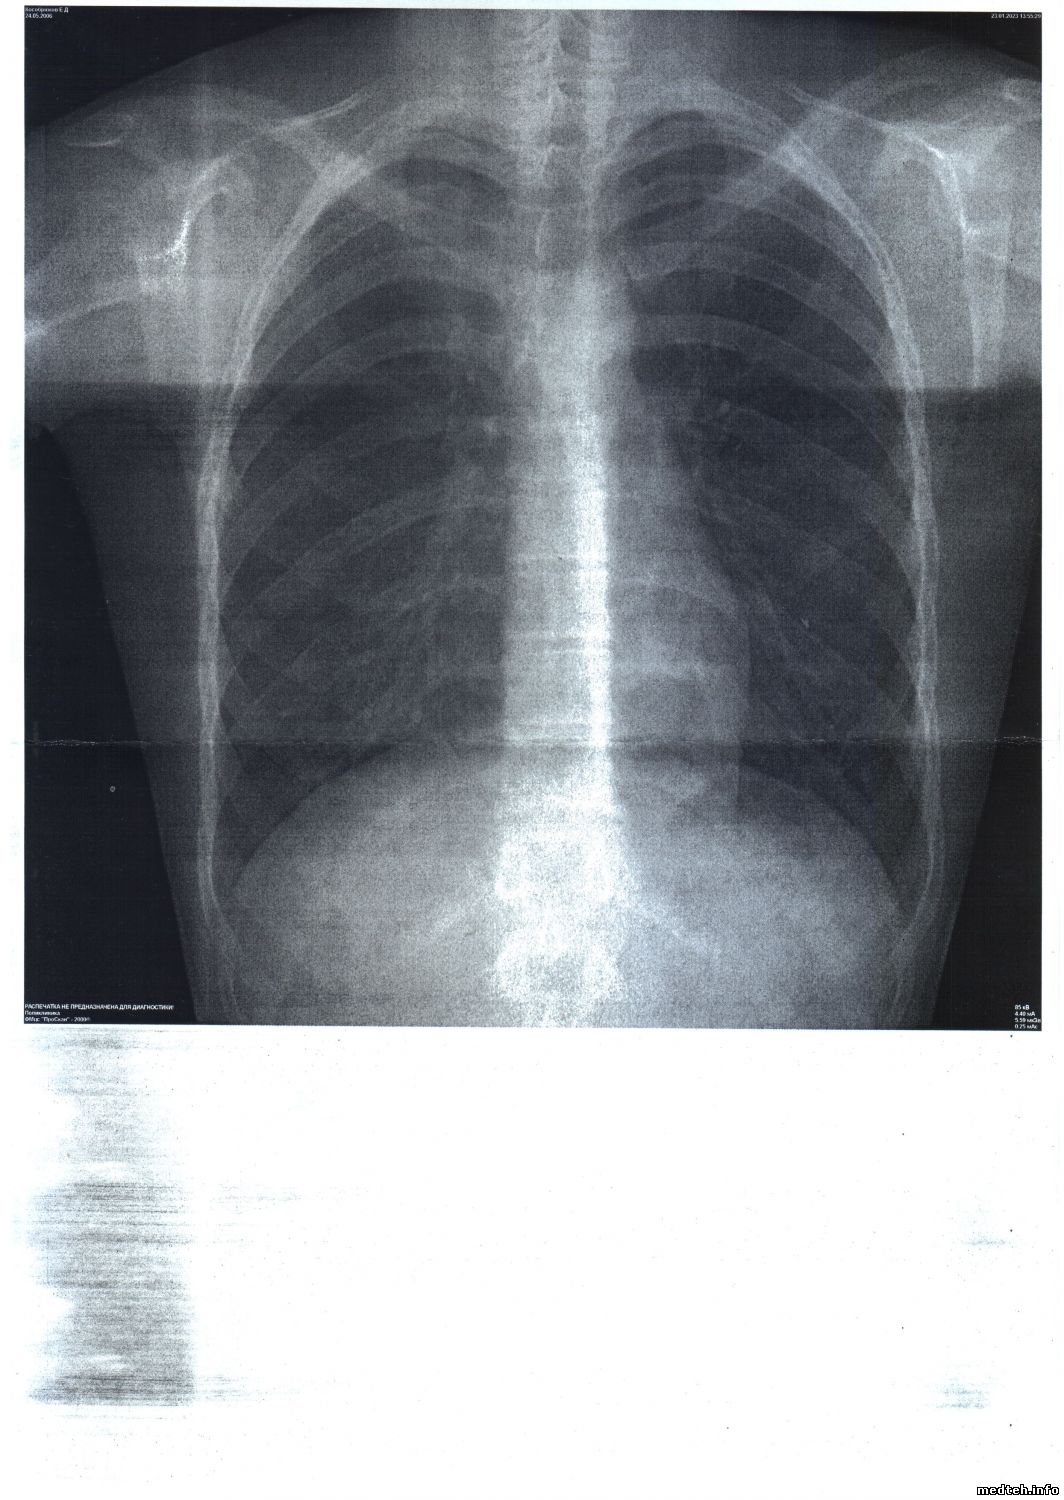

При печати снимка на бумагу слева вверху выводятся фамилия, инициалы и дата рождения пациента, а

слева внизу - название поликлиники и название аппарата.

Проблема в том, что они отображаются очень мелким шрифтом. Так, что и прочитать невозможно.

Файл снимка прилагаю.

6384429.jpg (213.4 Kb)

Ситуация следующая:

7846995.jpg (213.4 Kb)